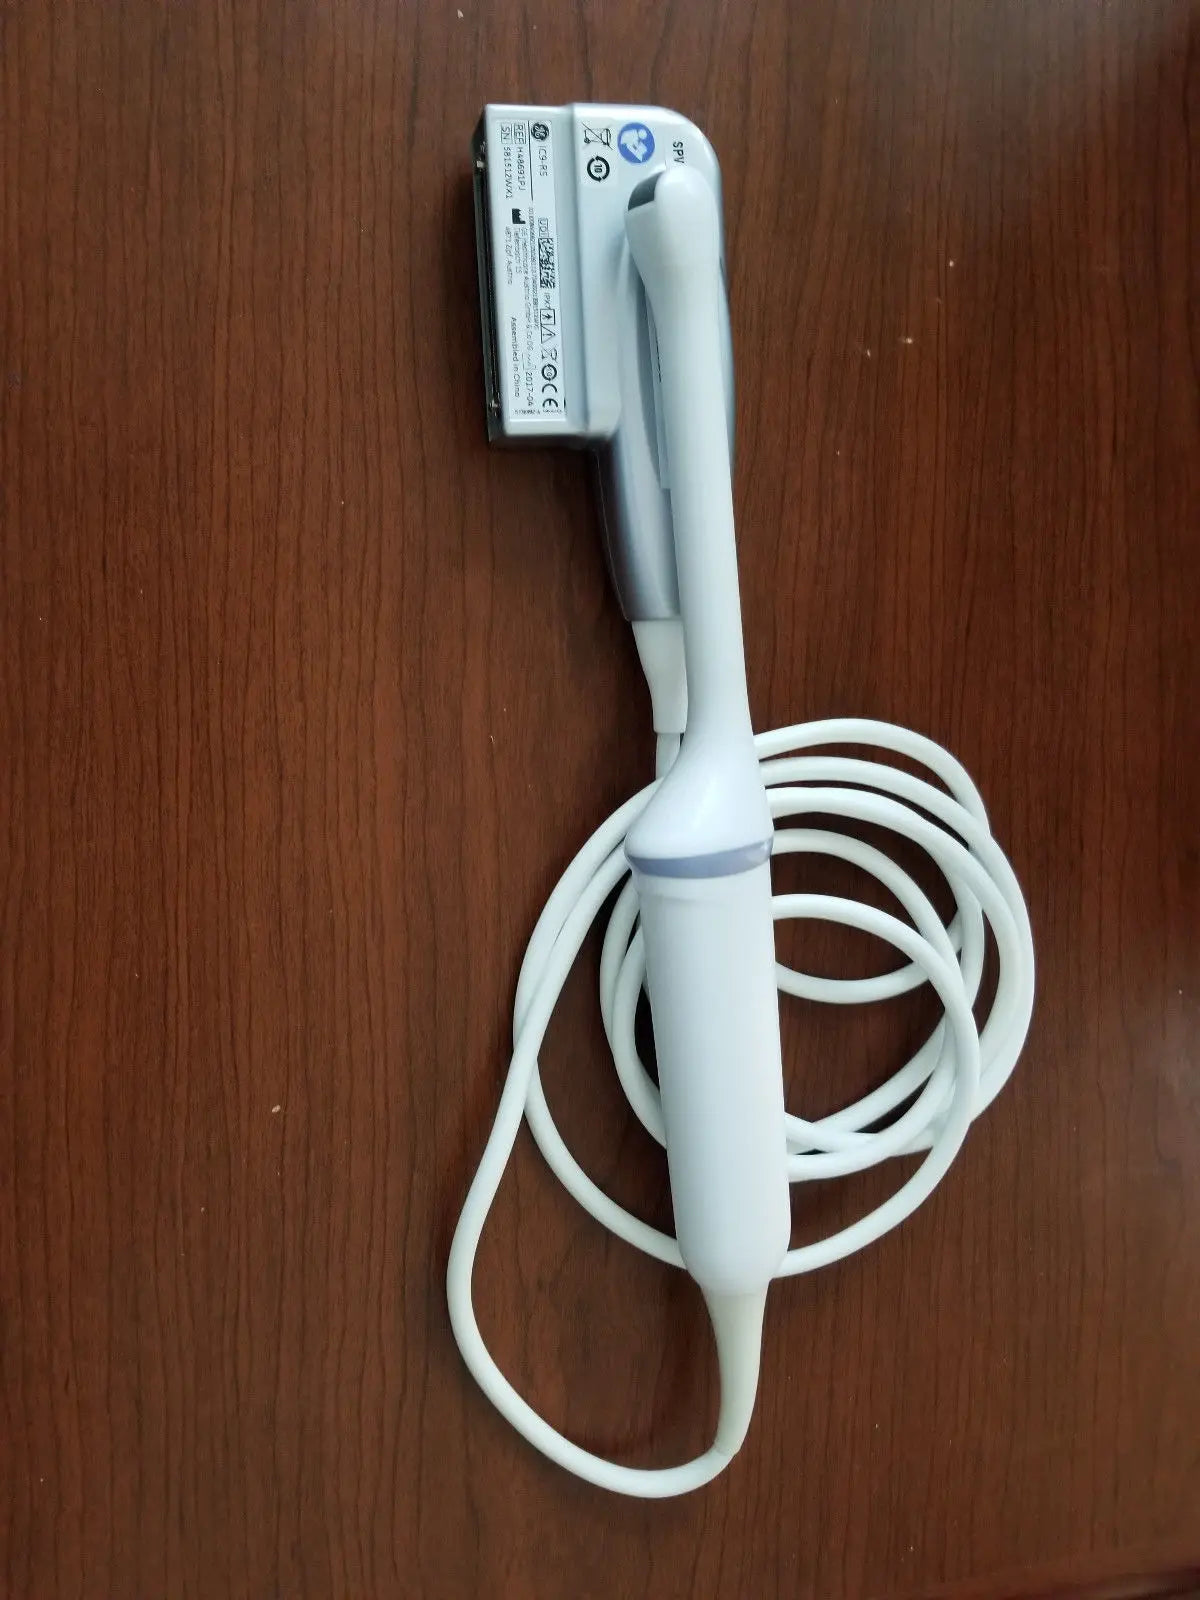

DIAGNOSTIC ULTRASOUND MACHINES FOR SALE

2017 GE IC9 -RS probe for GE Ultrasound

Sale price$ 8,395.14